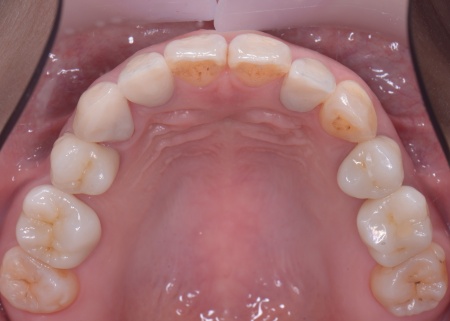

40代女性 矯正治療で噛み合わせを整えたあとセラミックの被せ物・詰め物で修復した症例

まずは矯正治療を優先し、噛み合わせが整ってから虫歯の再発リスクの低いセラミックの被せ物・詰め物などで歯の形態と機能を回復する方針を提案し、同意いただきました。

矯正治療終了後、改めてお口の中を確認したうえで、歯の状態に合わせ虫歯の除去や土台の修復を丁寧に行い、精密な型取りを実施しています。

最後に噛み合わせ全体のバランスを確認しながら新しく作製した被せ物や詰め物を装着し、見た目に問題がないか、噛み合わせが安定しているかを確認し、治療を終了しました。